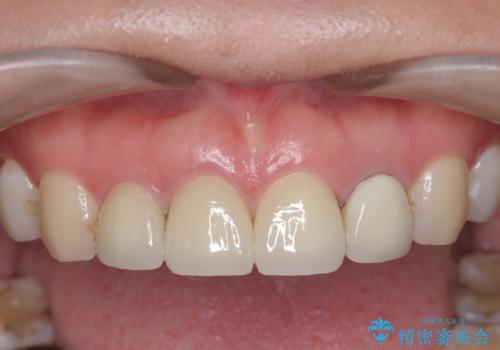

審美的なジルコニアクラウンを装着し、審美性が回復されたと満足いただくことができました。

- 前歯を天然の歯のようにきれいにやりかえたいと希望され来院されました。